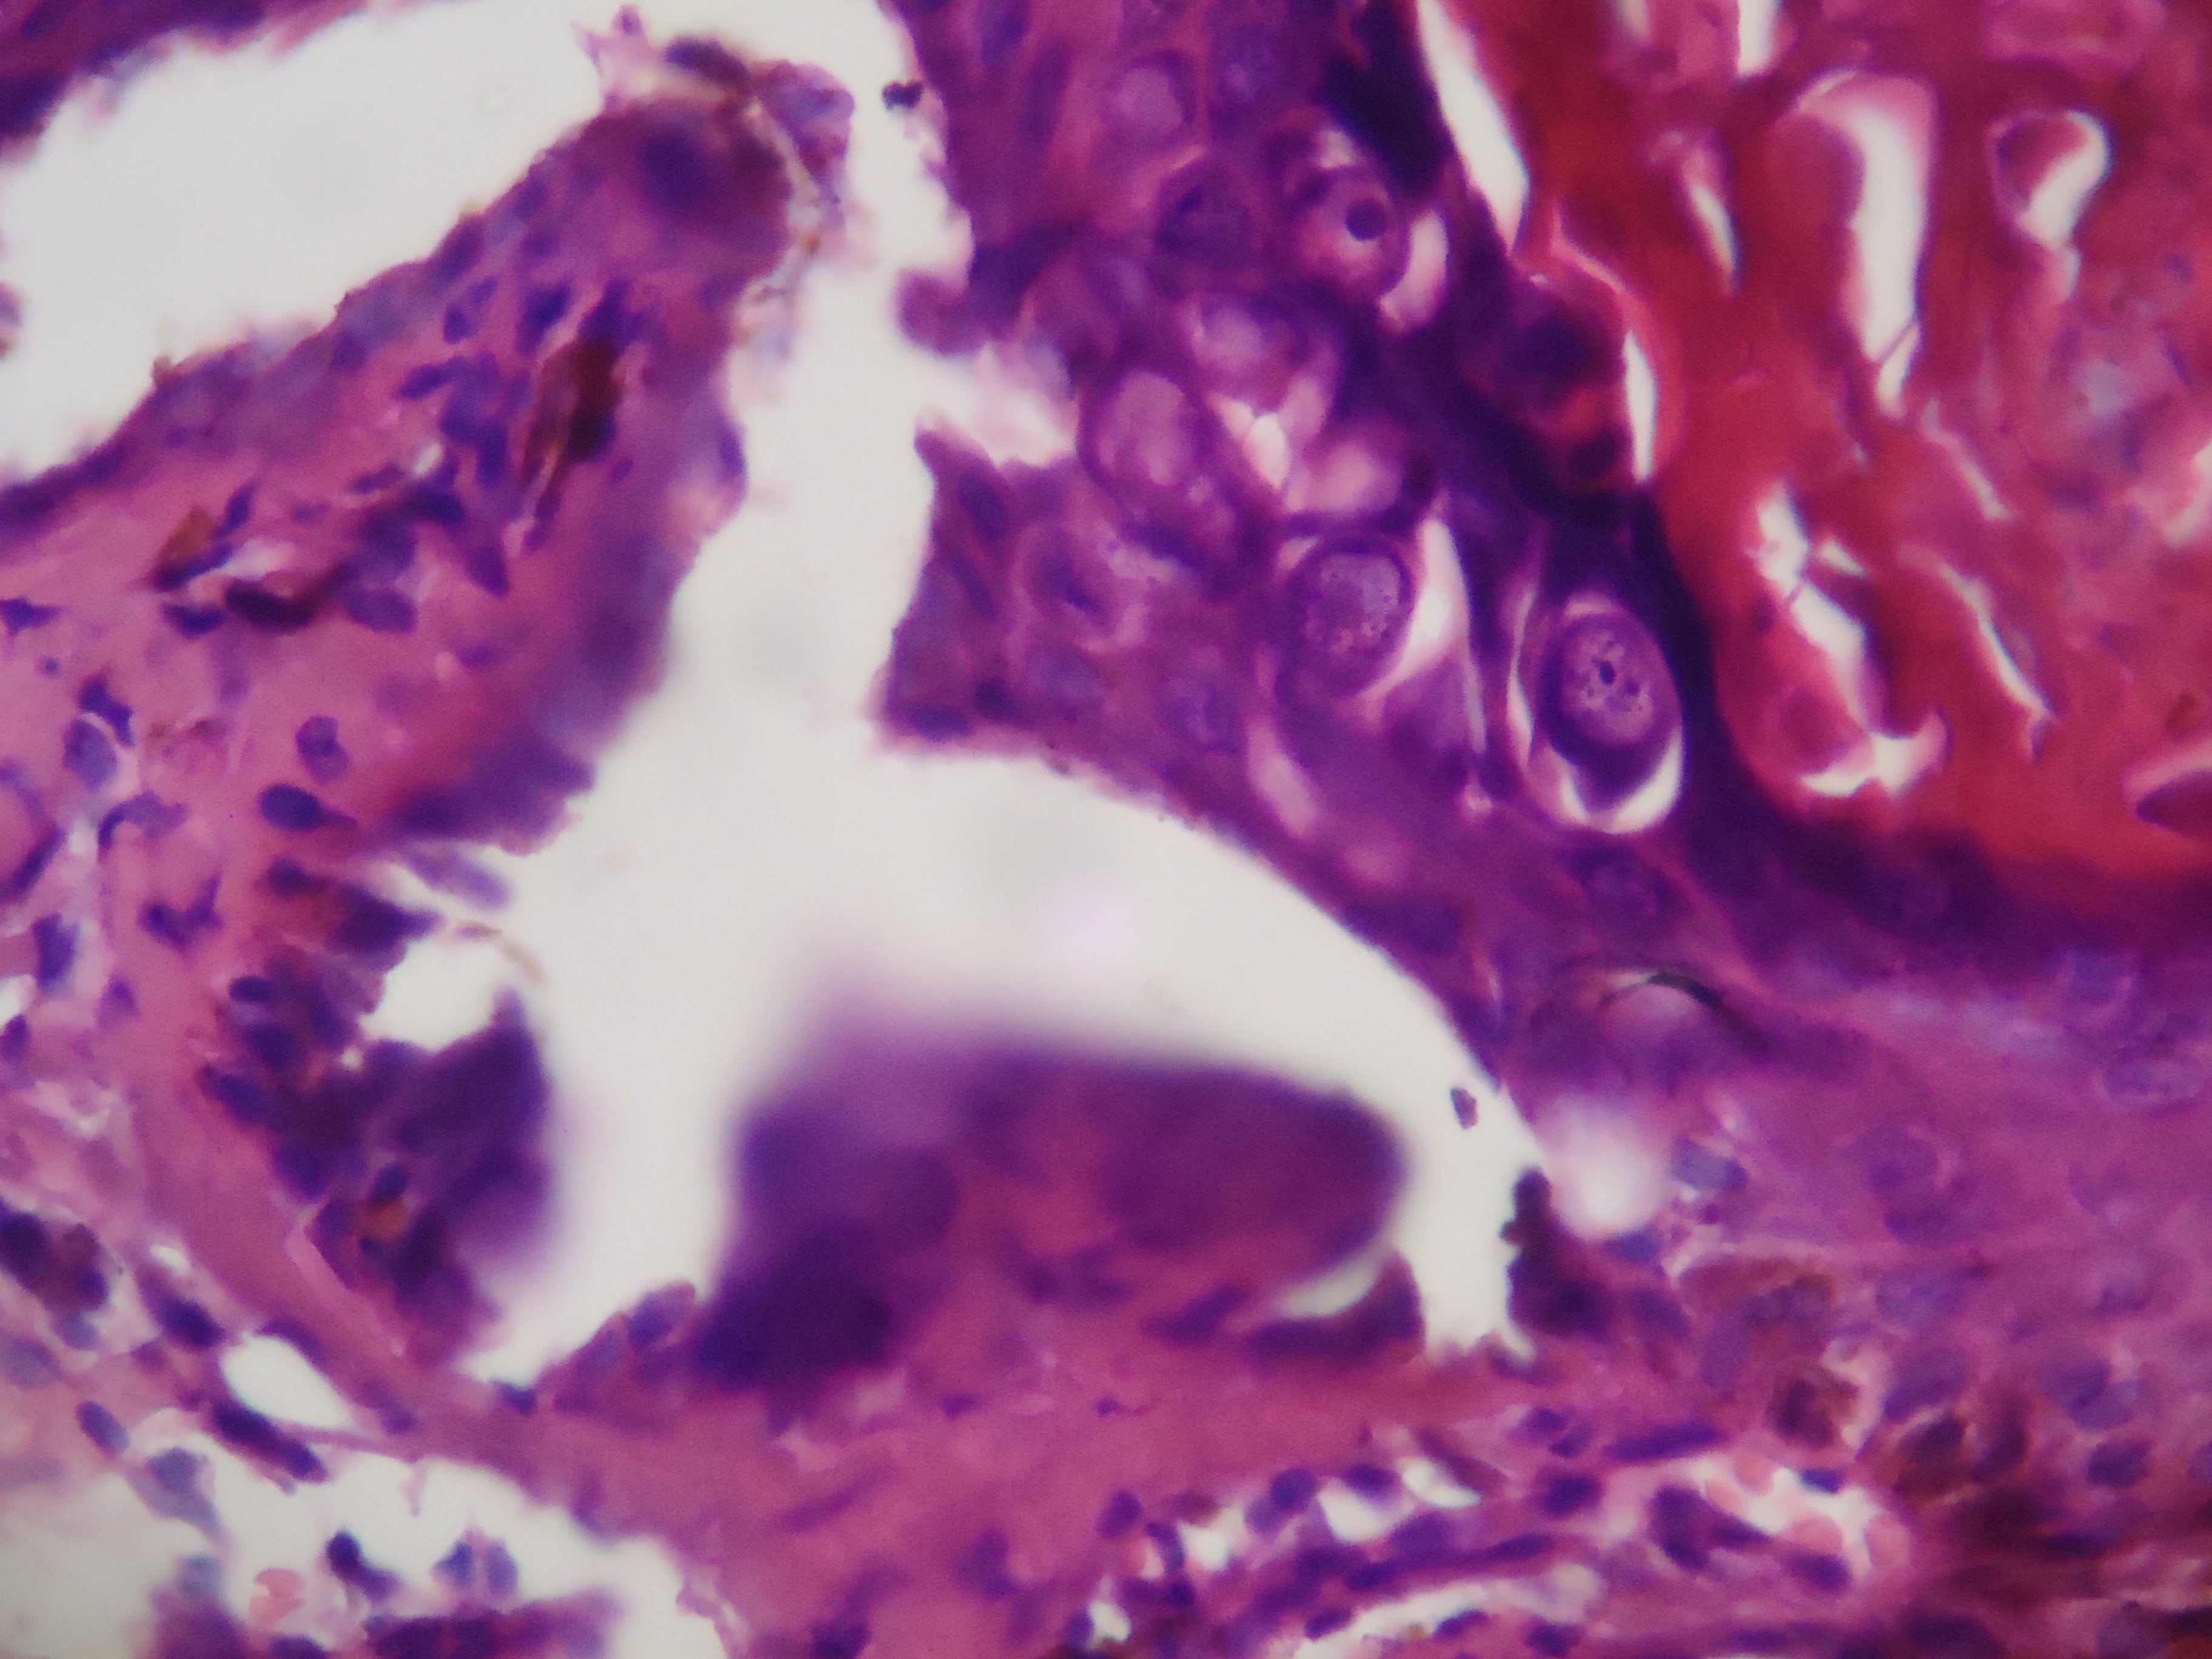

ENFEREMEDAD DE DARIER - HISTOPATOLOGIA